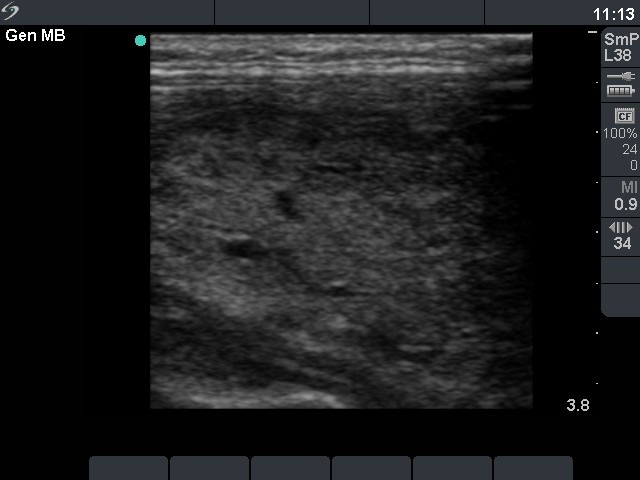

Graves' disease - Case 1049

Initial investigation (ultrasonographic picture 2)

Patient with a newly discovered hyperthyroidism

Right lobe, horizontal view

Right lobe, longitudinal scan. Around 50% of the thyroid is hypoechogenic.